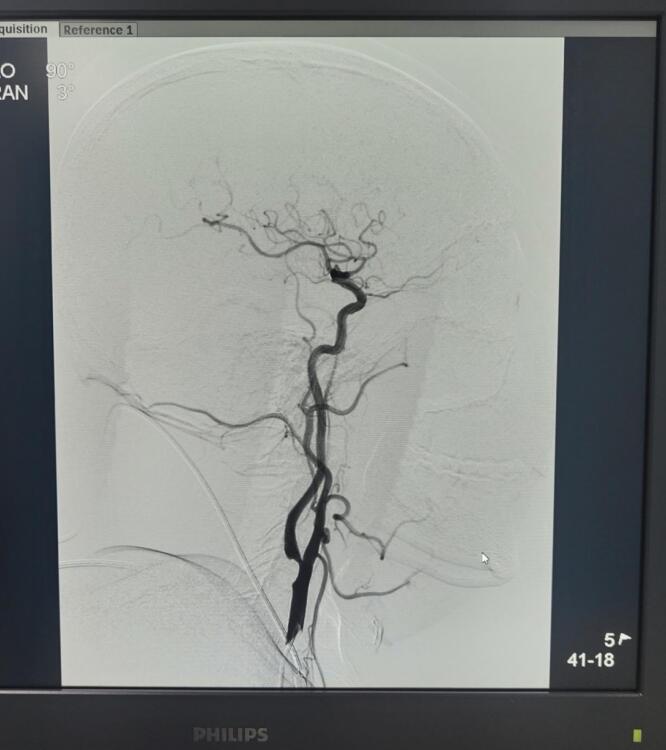

羅江區(qū)人民醫(yī)院開展首例全腦血管造影術(shù)

? ? ? ?7月31日下午,羅江區(qū)人民醫(yī)院神經(jīng)內(nèi)科成功開展首例全腦血管造影術(shù)主動脈弓造影術(shù),該項技術(shù)的順利開展填補了神經(jīng)內(nèi)科在該領(lǐng)域的空白,為羅江區(qū)域及周邊的腦血管病患者提供了新的現(xiàn)代化診療手段,提高了腦血管疾病的救治能力。

? ? ? ?據(jù)悉,患者向先生因反復(fù)頭暈20年,加重半年為主要癥狀入院,曾有過暈倒在地、意識喪失約5秒的病史。為了進一步明確顱內(nèi)血管病變情況,指導(dǎo)下一步治療,在與向先生及家屬充分溝通并取得同意后,神經(jīng)內(nèi)科主治醫(yī)師楊艷為向先生進行了全腦血管造影術(shù)及主動脈弓造影術(shù),造影診斷為右頸內(nèi)動脈重度狹窄、左頸內(nèi)動脈瘤。手術(shù)順利完成,向先生未訴任何特殊不適,生命體征平穩(wěn)。

? ? ? 全腦血管造影術(shù)是將造影劑注入到患者腦部的動脈使血管顯影,快速連續(xù)攝片,根據(jù)血管顯影的形態(tài)和部位來診斷腦血管病的方法。目前,全腦血管造影術(shù)對于腦血管患者的診斷,是一種行之有效的方法并作為國際上公認的“金標準”。羅江區(qū)人民醫(yī)院神經(jīng)內(nèi)科開展首例全腦血管造影術(shù)及主動脈弓造影術(shù)實現(xiàn)了腦血管介入診療技術(shù)零的突破,并在卒中預(yù)防和治療手段上邁上新的臺階,對降低腦血管病的致死率和致殘率具有重要意義。